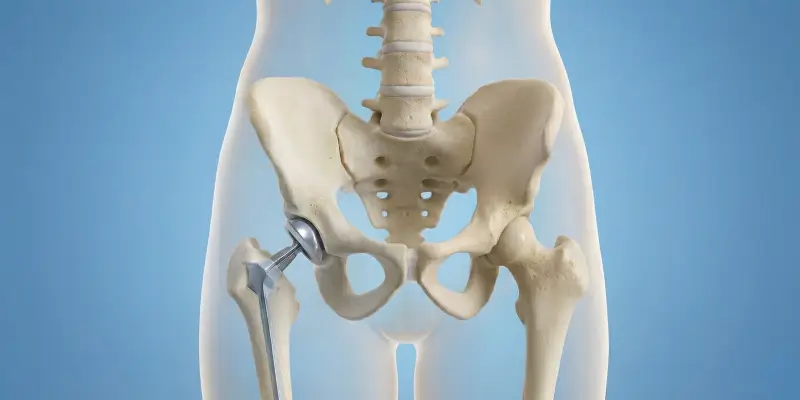

Total kalça protezi, kalça ekleminde ileri hasar ve deformitede aşınmış eklem yüzeylerinin metal, seramik veya polietilen protezle değiştirilmesidir. Endikasyonlar, cerrahi ve rehabilitasyon.